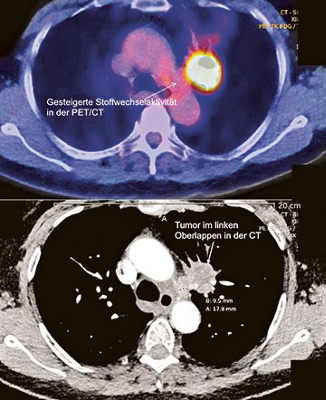

Das sogenannte Tumorstadium definiert sich aus der Kombination aus Primärtumor (Grösse, Lage), Lymphknotenbefall und eventuellem Vorhandensein von Fernmetastasen. Zur Abklärung stehen heute in der Klinik St. Anna die modernsten und hochsensiblen Untersuchungsmethoden zur Verfügung. Insbesondere mit Hilfe der PET/CT (Abb. 1) lässt sich eine Stadieneinteilung nach dem weltweiten Goldstandard durchführen. Neben der PET/CT kommt zum Ausschluss von Metastasen im Gehirn auch die Magnetresonanztomographie zum Einsatz.

Abb. 1

PET-Aufnahme der Lunge